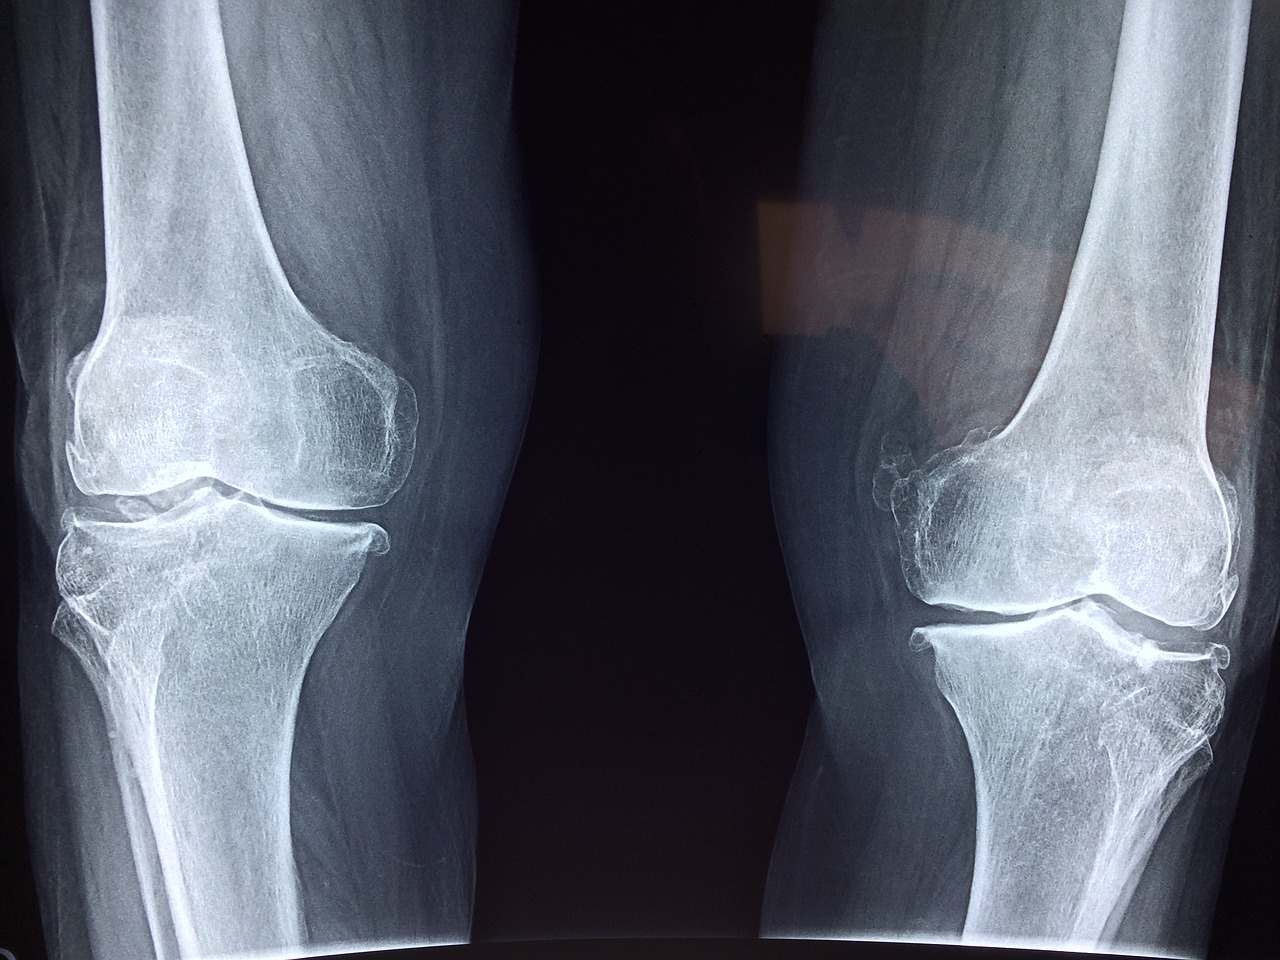

- leczy bóle mięśni i stawów

- wspomaga zdrowie kości

- bóle stawów

Herbata ze skrzypu pomoże usunąć kamienie nerkowe i oczyścić drogi moczowe. Oprócz tego wpłynie pozytywnie na gęstość kości, lecząc tym osteoporozę. Dzięki zawartości olejków eterycznych unieszkodliwi obecne w organizmie bakterie i pleśnie.

Specyfik na bóle stawów, kości i pleców